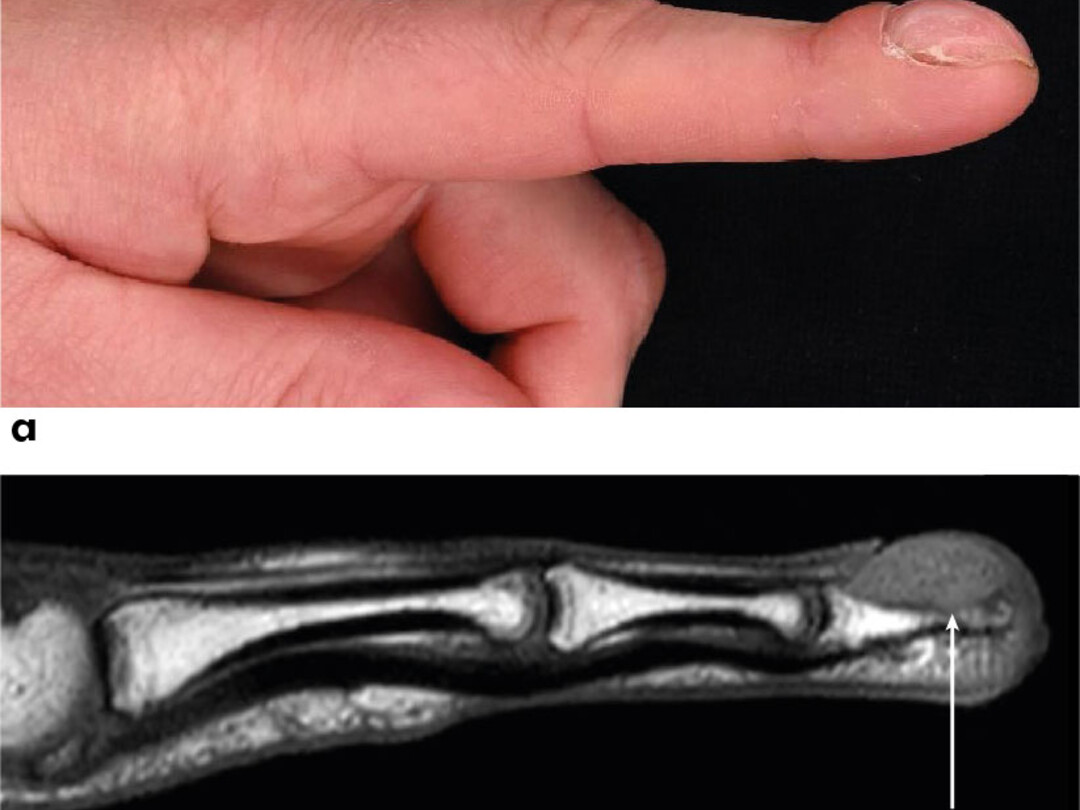

Een 33-jarige vrouw bezocht de afdeling Dermatologie met een sinds tien jaar bestaande, geleidelijk toenemende, asymptomatische afwijking aan de linker wijsvinger. De voorgeschiedenis en anamnese brachten geen uitlokkende factoren aan het licht, behoudens onychofagie. Bij lichamelijk onderzoek zagen wij een bolronde zwelling van de distale falanx van de linker wijsvinger, kort gezegd een trommelstokvinger (figuur 1a). Ter plaatse van de nagelriem was een zachte zwelling palpabel. De overige vingers waren niet afwijkend. Een MRI van de hand toonde een hyperintense afwijking uitgaande van de nagelriem met aantasting van de eindfalanx (figuur 1b). De patiënte werd voor excisie verwezen naar…